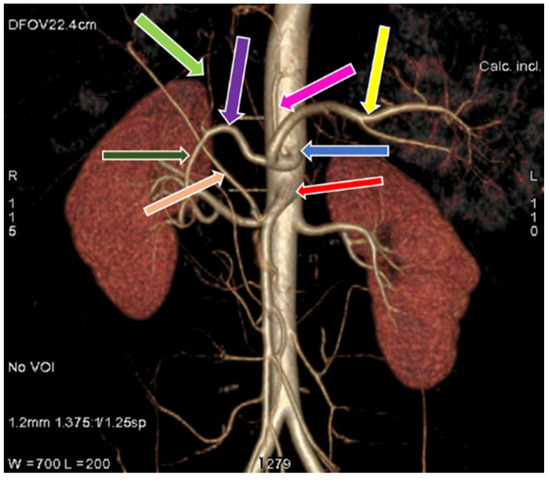

3.1. Variation in Origin and Branching Pattern of Celiac Trunk

3.2. Variation in Origin and Branching Pattern of Hepatic Artery